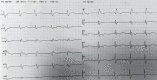

Elderly Man with Acute Chest Pain